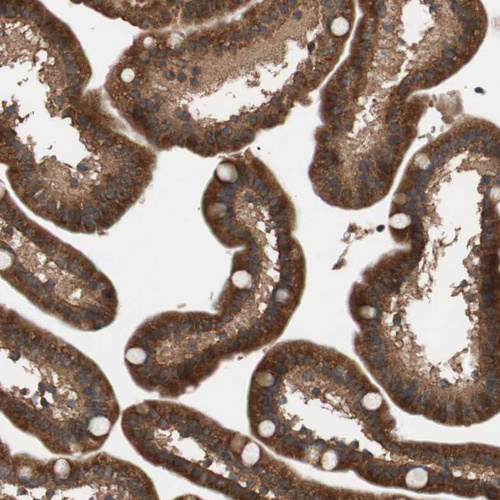

Immunohistochemical staining of human liver shows strong cytoplasmic positivity in hepatocytes.